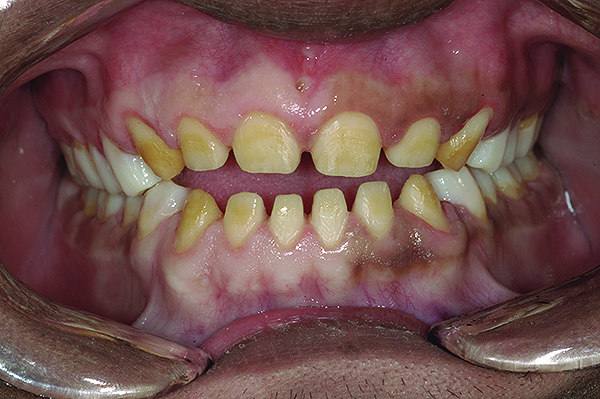

Figure 2. Preoperative 1:2 retracted frontal view.

Figure 2

A thorough clinical examination and analysis were carried out to assess the esthetic and functional problems of the patient (Figure 2 through Figure 7). The medical history was non-contributory, except for mild leukoderma. Temporomandibular joint (TMJ) function was within normal range.

The authors report on a 21-year-old patient who presented with severe discoloration and mild sensitivity of teeth (Figure 1). The teeth visible in his smile were very short, unsightly, and unbecoming for his age.